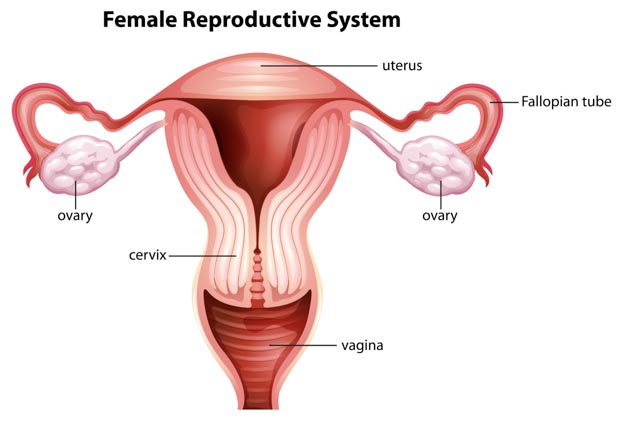

Acupuncture and herbs clear fallopian tube obstructions and restore fertility. Researchers from the Maternal and Child Health Care Hospital of Puyang City tested a four part Traditional Chinese Medicine (TCM) protocol for restoring fallopian tube patency. The acupuncture and herbal medicine protocol led to the successful clearing of hydrosalpinx and other fallopian tube obstructions. In addition, the acupuncture and herbal medicine protocol outperformed a control group receiving medications.

Two-hundred patients with fallopian tube obstruction related infertility were equally and randomly divided into two groups. The Traditional Chinese Medicine group received protocolized care of acupuncture, cupping, oral intake herbal medicine, external poultice herbal medicine, and an herbal enema. The purpose of the enema is to absorb herbal medicines into the reproductive system through the intestines. A Traditional Chinese Medicine maxim is that the large intestine is the “friend of the uterus.” This reflects the fact that the large intestine and uterus are physically beside each other and run parallel in one part of the body. The enema is a form of herbal medicine application to the affected region.

The study provides consistent clinical and objective measure improvements. Fallopian tube patency was tested using fluid backflow measurements and gas flow measurements. The researchers tabulated the data and concluded that the TCM protocol is highly effective for the treatment of fallopian tube obstruction related fertility. In addition, pregnancy rate improvements confirm the conclusions based on the fluid and gas flow findings.